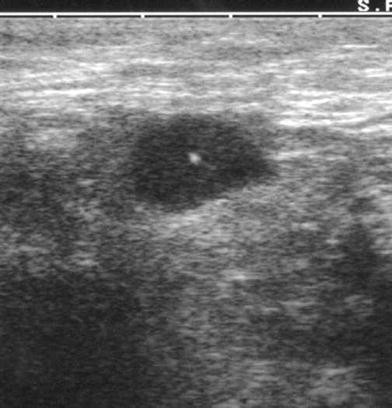

Fnac aspiration cytology from a variety of organ sites is useful in the determination of pathologic states particularly neoplasms inflammatory conditions. It is a great way to investigate swellings tumours and swollen lymph nodes. Fine needle aspiration cytology fnac of the lymph node is a simple diagnostic tool to diagnose suspected and unsuspected secondary and primary lymph node malignancy.

In addition to testing lumps and bumps fnac biopsy is also useful in the diagnosis of other diseases such as tuberculosis infection of the lymph nodes which is common in the country. Aspiration of superficial enlarged lymph nodes was performed free hand using a 23 g needle mounted on a cameco handle. It is a simple and rapid diagnostic test economic primary investigation with minimal trauma easily carried out in opd.